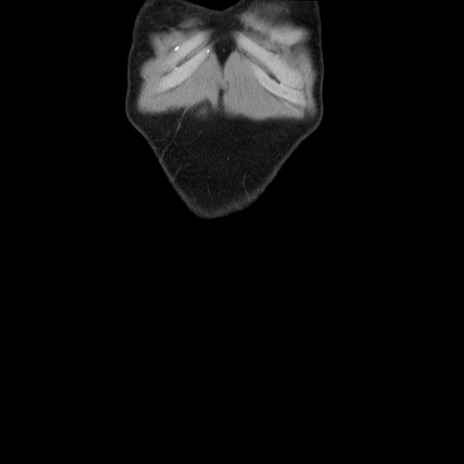

横断像